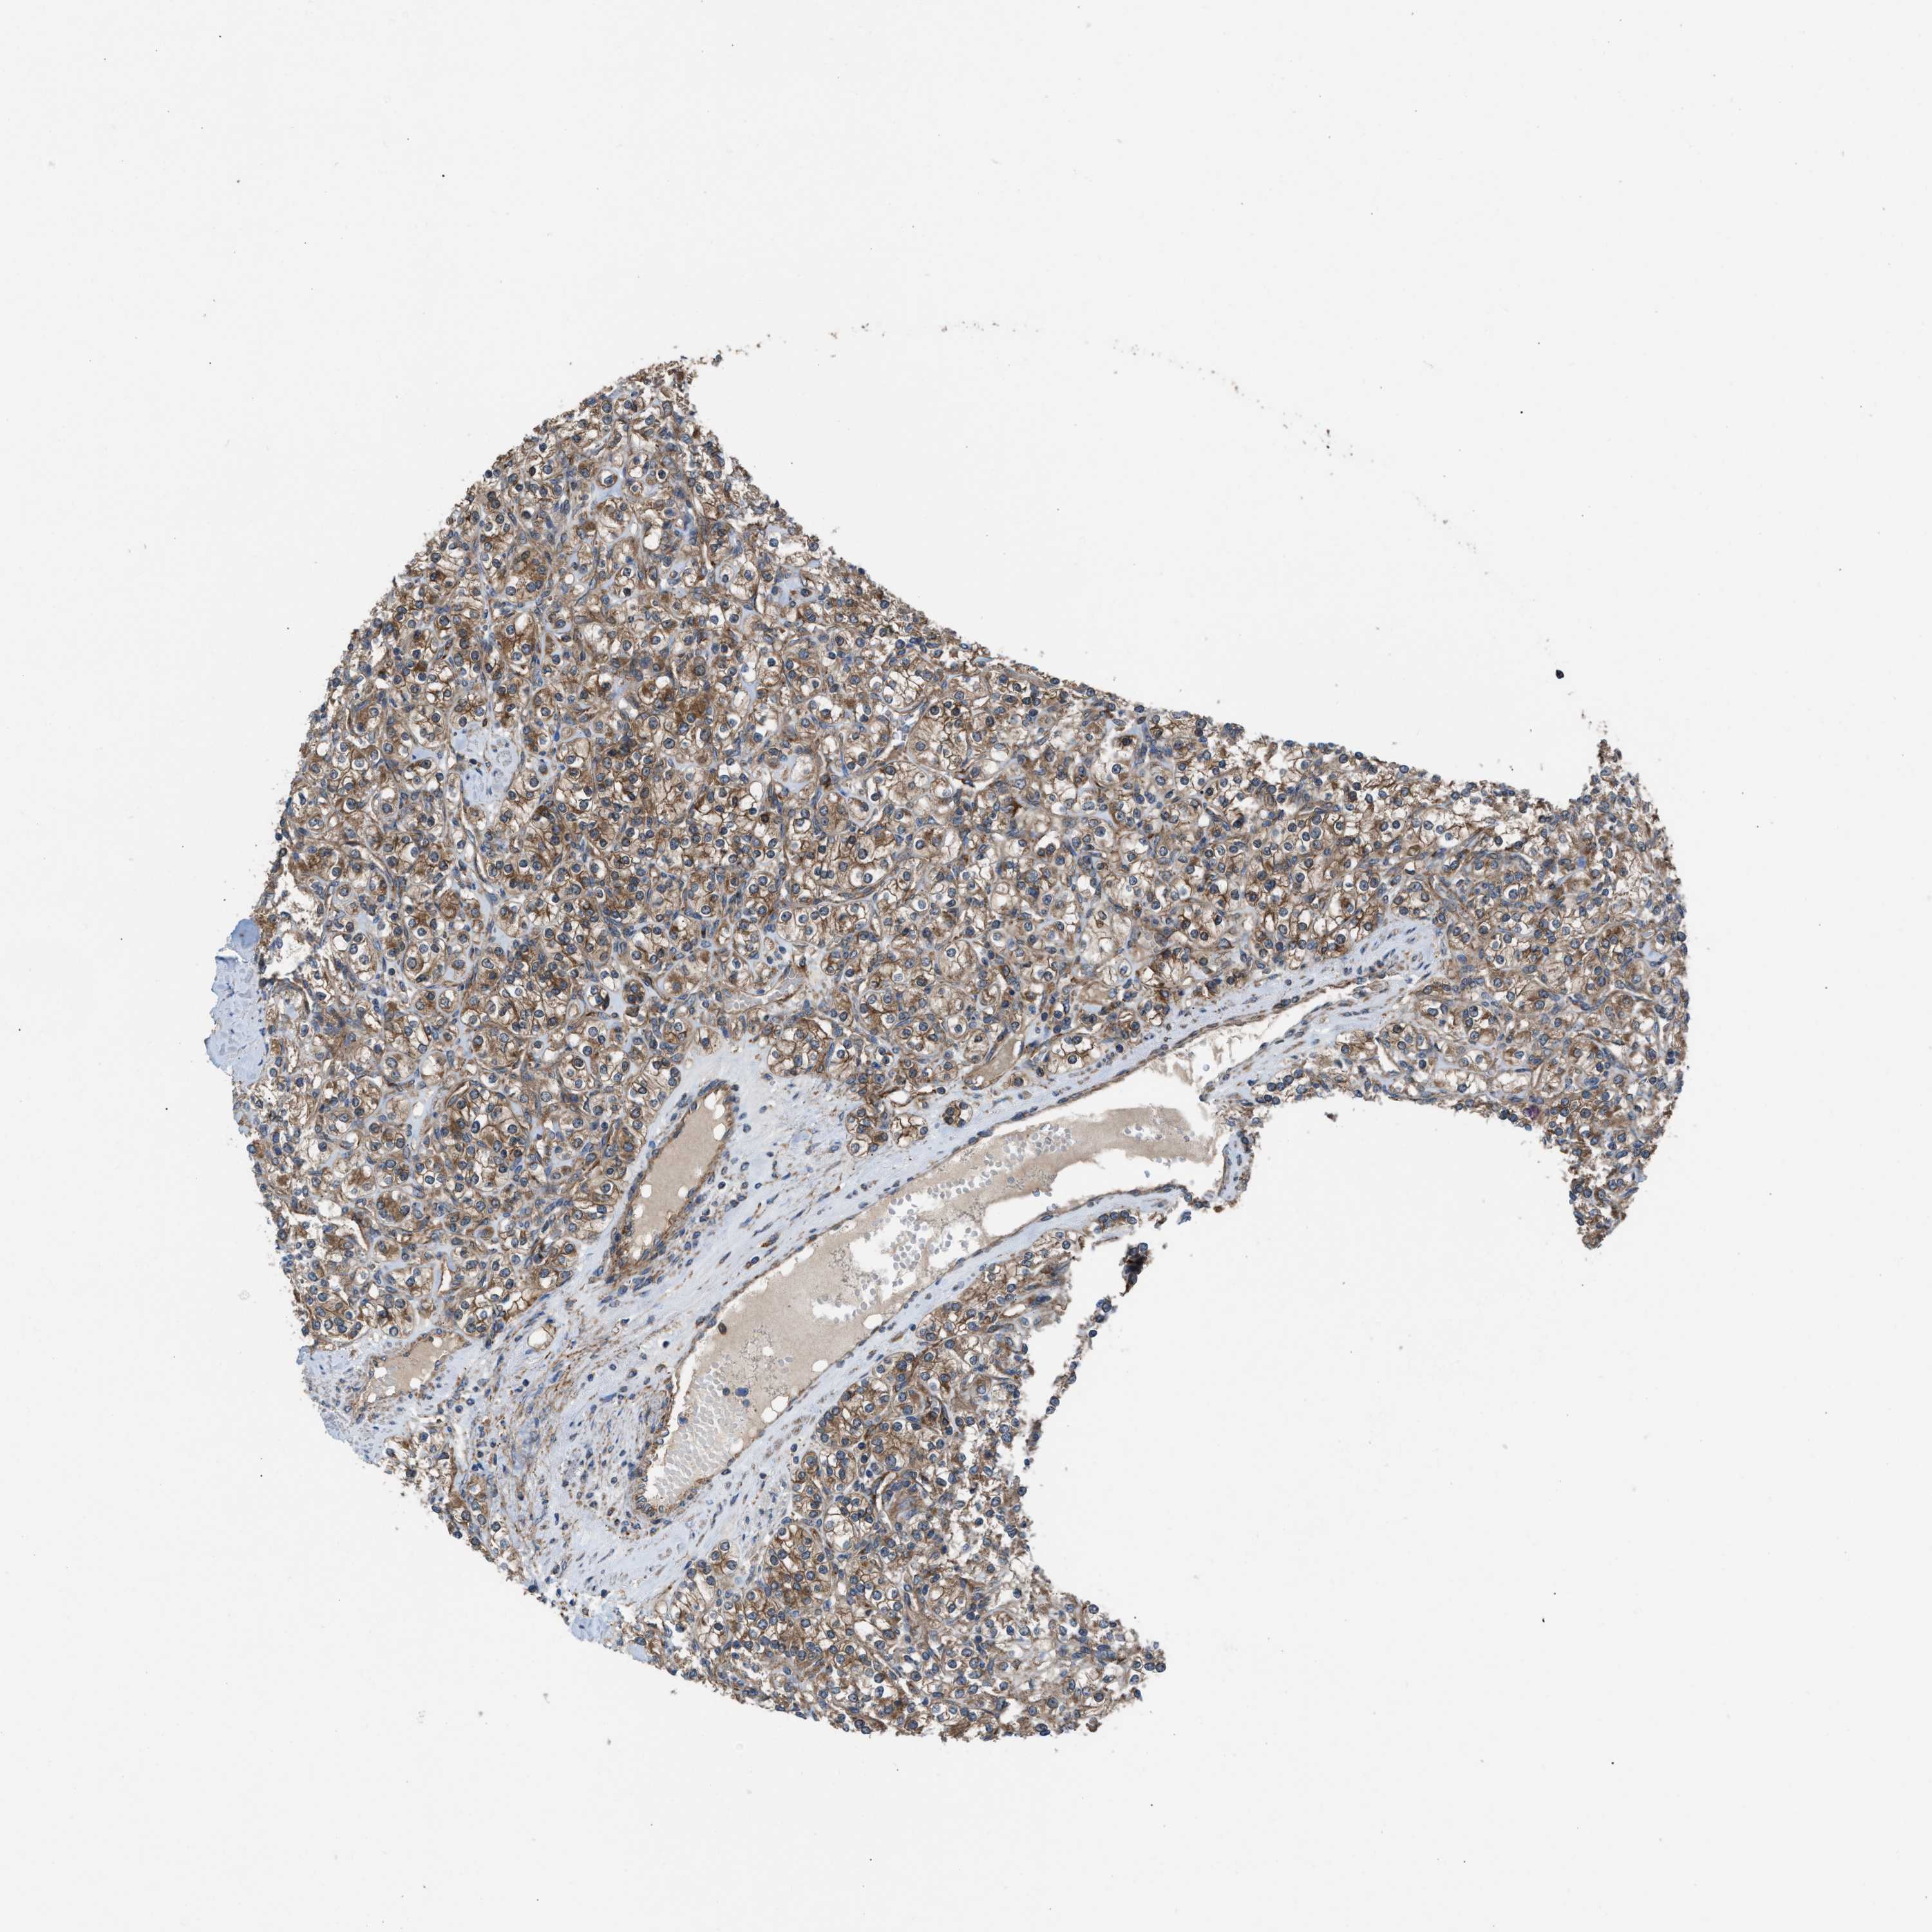

KIDNEY RENAL PAPILLARY CELL CARCINOMA (TCGA) - Interactive survival scatter ploti

The Survival Scatter plot shows the clinical status (i.e. dead or alive) for all individuals in the patient cohort, based on the same data that underlies the corresponding Kaplan-Meier plots. Patients that are alive at last time for follow-up are shown in blue and patients who have died during the study are shown in red.

The x-axis shows the expression levels (FPKM) of the investigated gene in the tumor tissue at the time of diagnosis. The y-axis shows the follow-up time after diagnosis (years). Both axes are complimented with kernel density curves demonstrating the data density over the axes. The top density plot shows the expression levels (FPKM) distribution among dead (red) and alive patients (blue). The right density plot shows the data density of the survived years of dead patients with high and low expression levels respectively, stratified using the cutoff indicated by the vertical dashed line through the Survival Scatter plot. This cutoff is automatically defined based on the FPKM cutoff that minimizes the p-score. The cutoff can be changed by dragging the vertical line or by entering a cutoff value in the square labeled "Current cut-off".

Under the Survival Scatter plot the p-score landscape (black curve; left axis) is shown together with dead median separation (red curve; right axis). Dead median separation is the difference in median mRNA expression between patients who have died with high and low expression, respectively. It is calculated as follows: median FPKM expression of dead patients with high expression - median FPKM expression of dead patients with low expression. This is intended to aid the user in visually exploring custom cutoffs and the associated p-scores and dead median separation.

Individual patient data is displayed and can be filtered by clicking on one or more of the category buttons on the top of the page. Categories describing expression level and patient information include: high, low, alive, dead, female, male and tumor stages. The scale of the x-axis can be toggled between linear and log-scale by clicking on the "x log" button. Mouse-over function shows TCGA ID, patient information and mRNA expression (FPKM) for each patient.

& Survival analysisi

Kaplan-Meier plots summarize results from analysis of correlation between mRNA expression level and patient survival. Patients were divided based on level of expression into one of the two groups "low" (under cut off) or "high" (over cut off). X-axis shows time for survival (years) and y-axis shows the probability of survival, where 1.0 corresponds to 100 percent.

ZNF614 is not prognostic in Kidney Renal Papillary Cell Carcinoma (TCGA)

Best expression cut offi

Based on the FPKM value of each gene, patients were classified into two groups and association between prognosis (survival) and gene expression (FPKM) was examined. The best expression cut-off refers the FPKM value that yields maximal difference with regard to survival between the two groups at the lowest log-rank P-value. Best expression cut-off was selected based on survival analysis .

When clicking on this number, the vertical dashed line indicating cut-off, the interactive survival plot, and the Kaplan-Meier curve will be adjusted to show results based on the best expression cut-off.